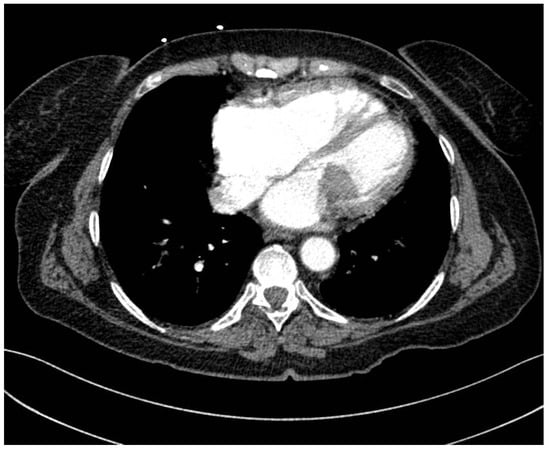

Rare Case of Grade 3 Undifferentiated Pleomorphic Sarcoma in Left Atrium, Mitral Valve, and Papillary Muscle

2. Case Report